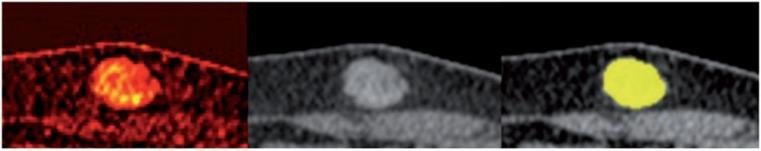

Supplementary functional information can contribute to assess response in targeted therapies. The aim of this study was to evaluate semi-automatic RECIST plus iodine uptake (IU) determination in melanoma metastases under BRAF inhibitor (vemurafenib) therapy using dual-energy computed tomography (DECT).

METHODS

Nine patients with stage IV melanoma treated with a BRAF inhibitor were included. Contrast-enhanced DECT was performed before and twice after treatment onset. Changes in tumor size were assessed according to RECIST. Quantification of IU (absolute value for total IU (mg) and volume-normalized IU (mg/ml)) was based on semi-automatic tumor volume segmentation. The decrease compared with baseline was calculated.

补充功能信息有助于评估靶向治疗的反应。本研究旨在评估黑色素瘤转移患者在 BRAF 抑制剂(vemurafenib)治疗下使用双能 CT(DECT)的 RECIST 联合碘摄取(IU)的半自动测定。

方法

纳入 9 例接受 BRAF 抑制剂治疗的 IV 期黑色素瘤患者。在治疗开始前和开始后两次进行增强 DECT。根据 RECIST 评估肿瘤大小的变化。IU 的定量(总 IU(mg)和体积归一化 IU(mg/ml)的绝对值)基于半自动肿瘤体积分割。与基线相比计算下降值。